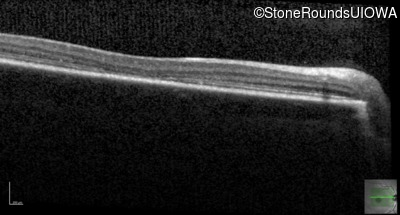

Optical Coherence Tomography - Left - 20/80

Exemplar / OCT Stack